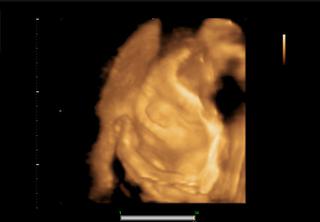

@bettyx no zrovna dobré správy nemám, len mám k tomu iný postoj.. 😠 na poradni som dnes začala špiniť... tak mi doky rovno povedal, že mám nejakú infekciu, a že keď pôjde čerstvá krv, hajde do nemocnice.. 😖 Dal mi hneď lieky do pošvy, Macmiror, k tomu ten znížený kreatinín.. a poslal ma na krčné, lebo mám od malého asi nejakého streptokoka, bolí ma hrozne hrdlo a už týždeň sa trápim. Aby toho nebolo dosť, tak som bola potom u známeho na 4D utlrazvuku a ten mi povedal, že malý má pupočník pod bradou, takže mám sledovať pohyby a ozvi, ak by sa mi niečo nezdalo, utekať do nemocnice.. 😠 Tak už budem ďalšie tri mesiace v pohotovosti.. Tiež mám furt čosi, ale už som si povedala, bude, ako byť má... Ale malý je taký nádherný.. taká som bola šťastná.. Bojím sa veľmi oňho, ale nepočúvam blbé reči... riadim sa vnútorným pocitom... A ten má veľkú vieru, že nám boh pomôže a všetko bude dobré... Prikladám foto 😵